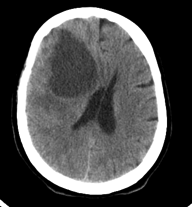

Quais os achados radiológicos?

Qual a principal hipótese diagnóstica?

herniação subfalcina, lesão hipodensa em lobo frontal e parietal direitos, efeito de massa sobre o ventrículo direito com desvio da linha média à esquerda